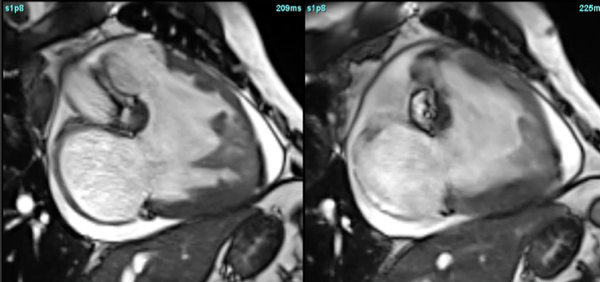

Isolated RV infarction.